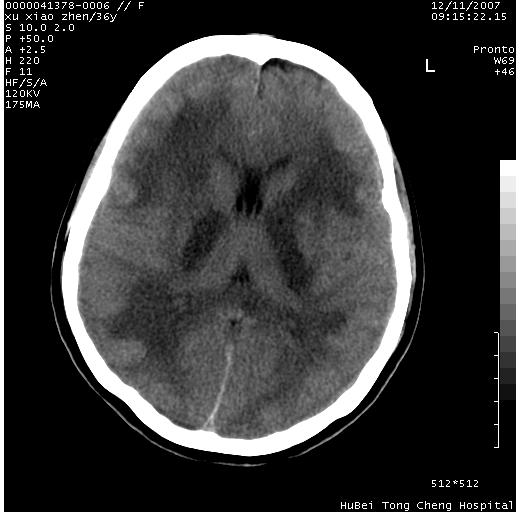

以下是引用wzr在2007-12-12 18:58:00的发言:[br]以脑白质受累,脑肿胀明显,脑室变窄,多考虑炎性改变,建议进一步ce或mri明确.

以下是引用wqs571018在2007-12-12 19:48:00的发言:[br]脑白质受累,脑肿胀明显,脑室变窄,多考虑炎性改变,脑膜炎可能性大;建议mri明确.。